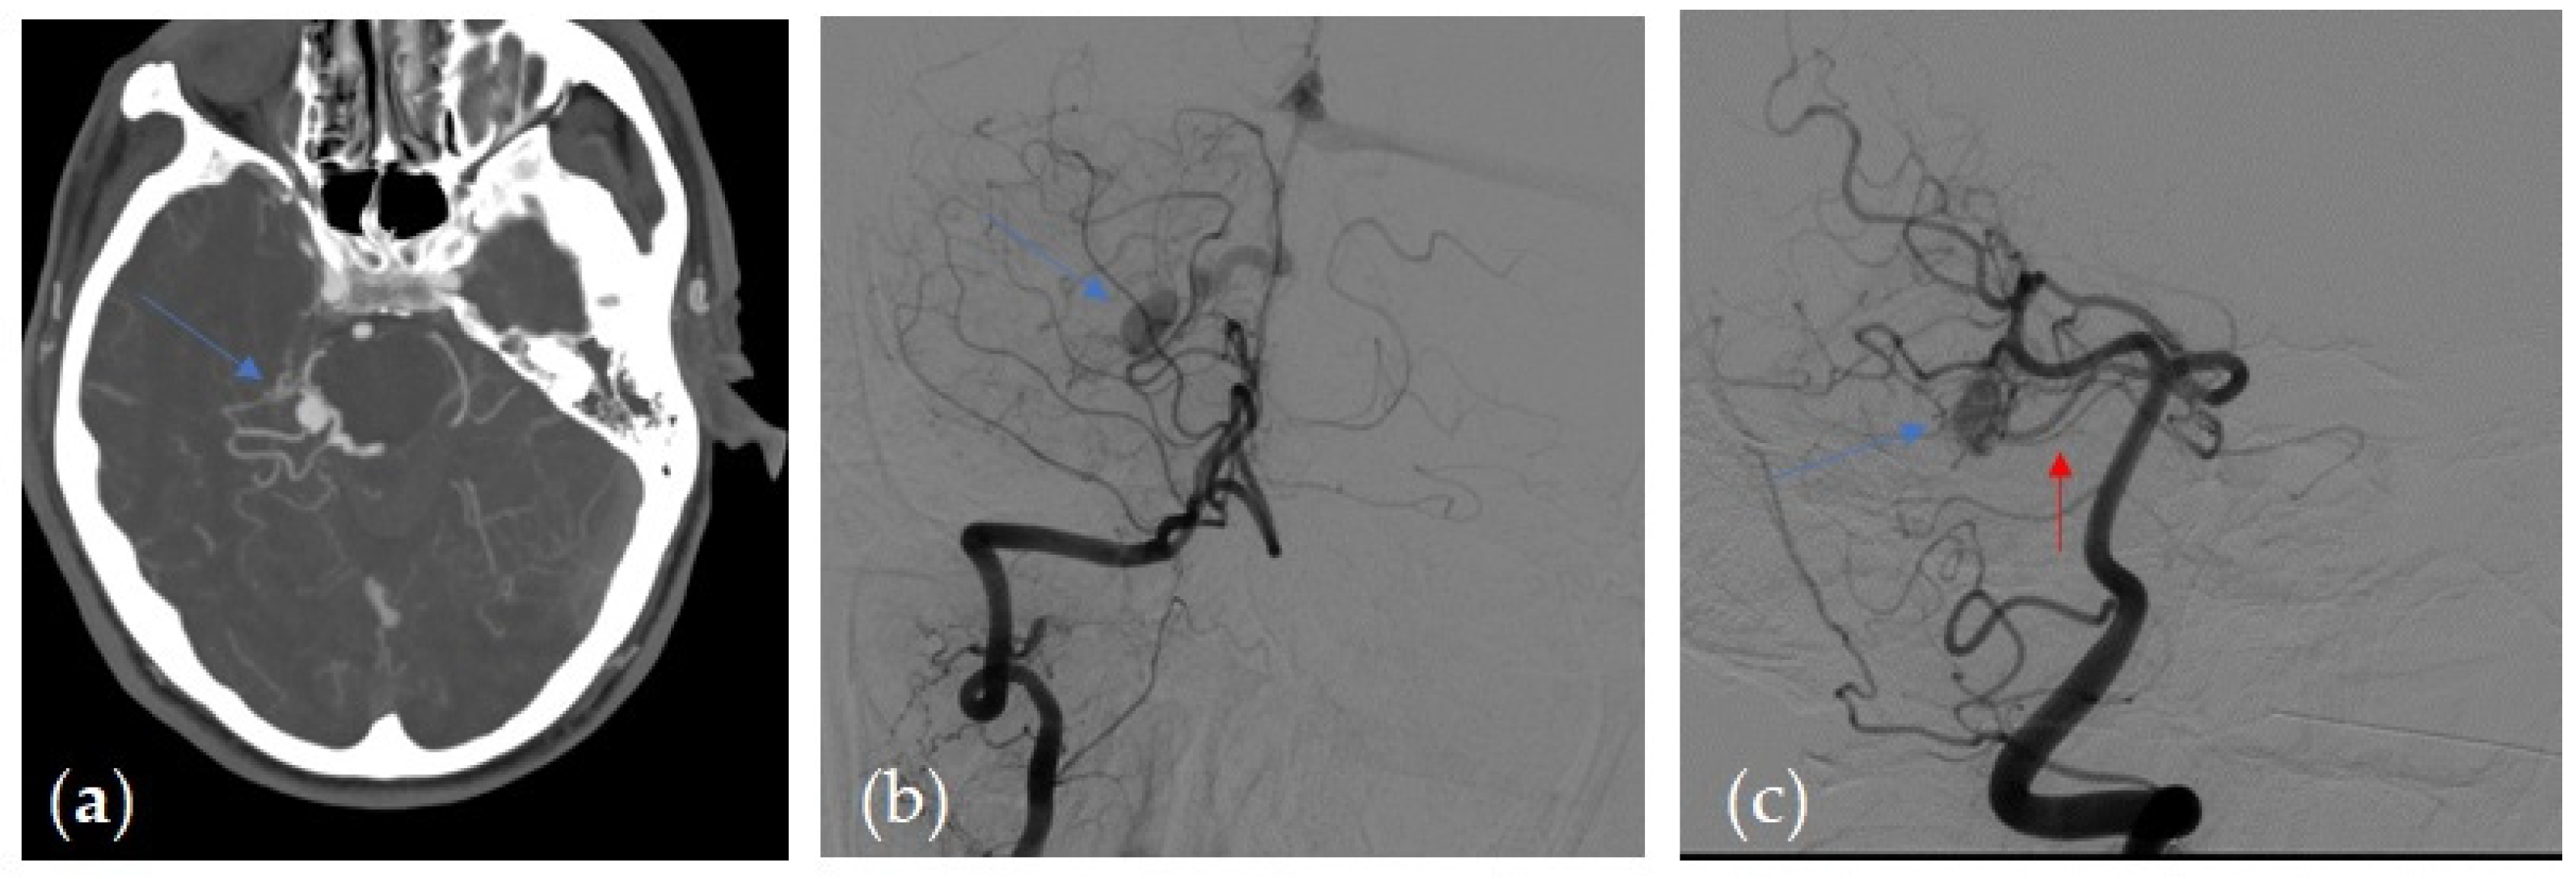

| Brain Angio CT Positive Findings | No. of Patients |

|---|---|

| Asymmetric and/or dilated feeding arteries | 7 |

| Numerous and engorged cortical veins | 15 |

| Sinus findings: | |

| 8 |

| 10 |

| 4 |

| Transcalvarial channels | 4 |